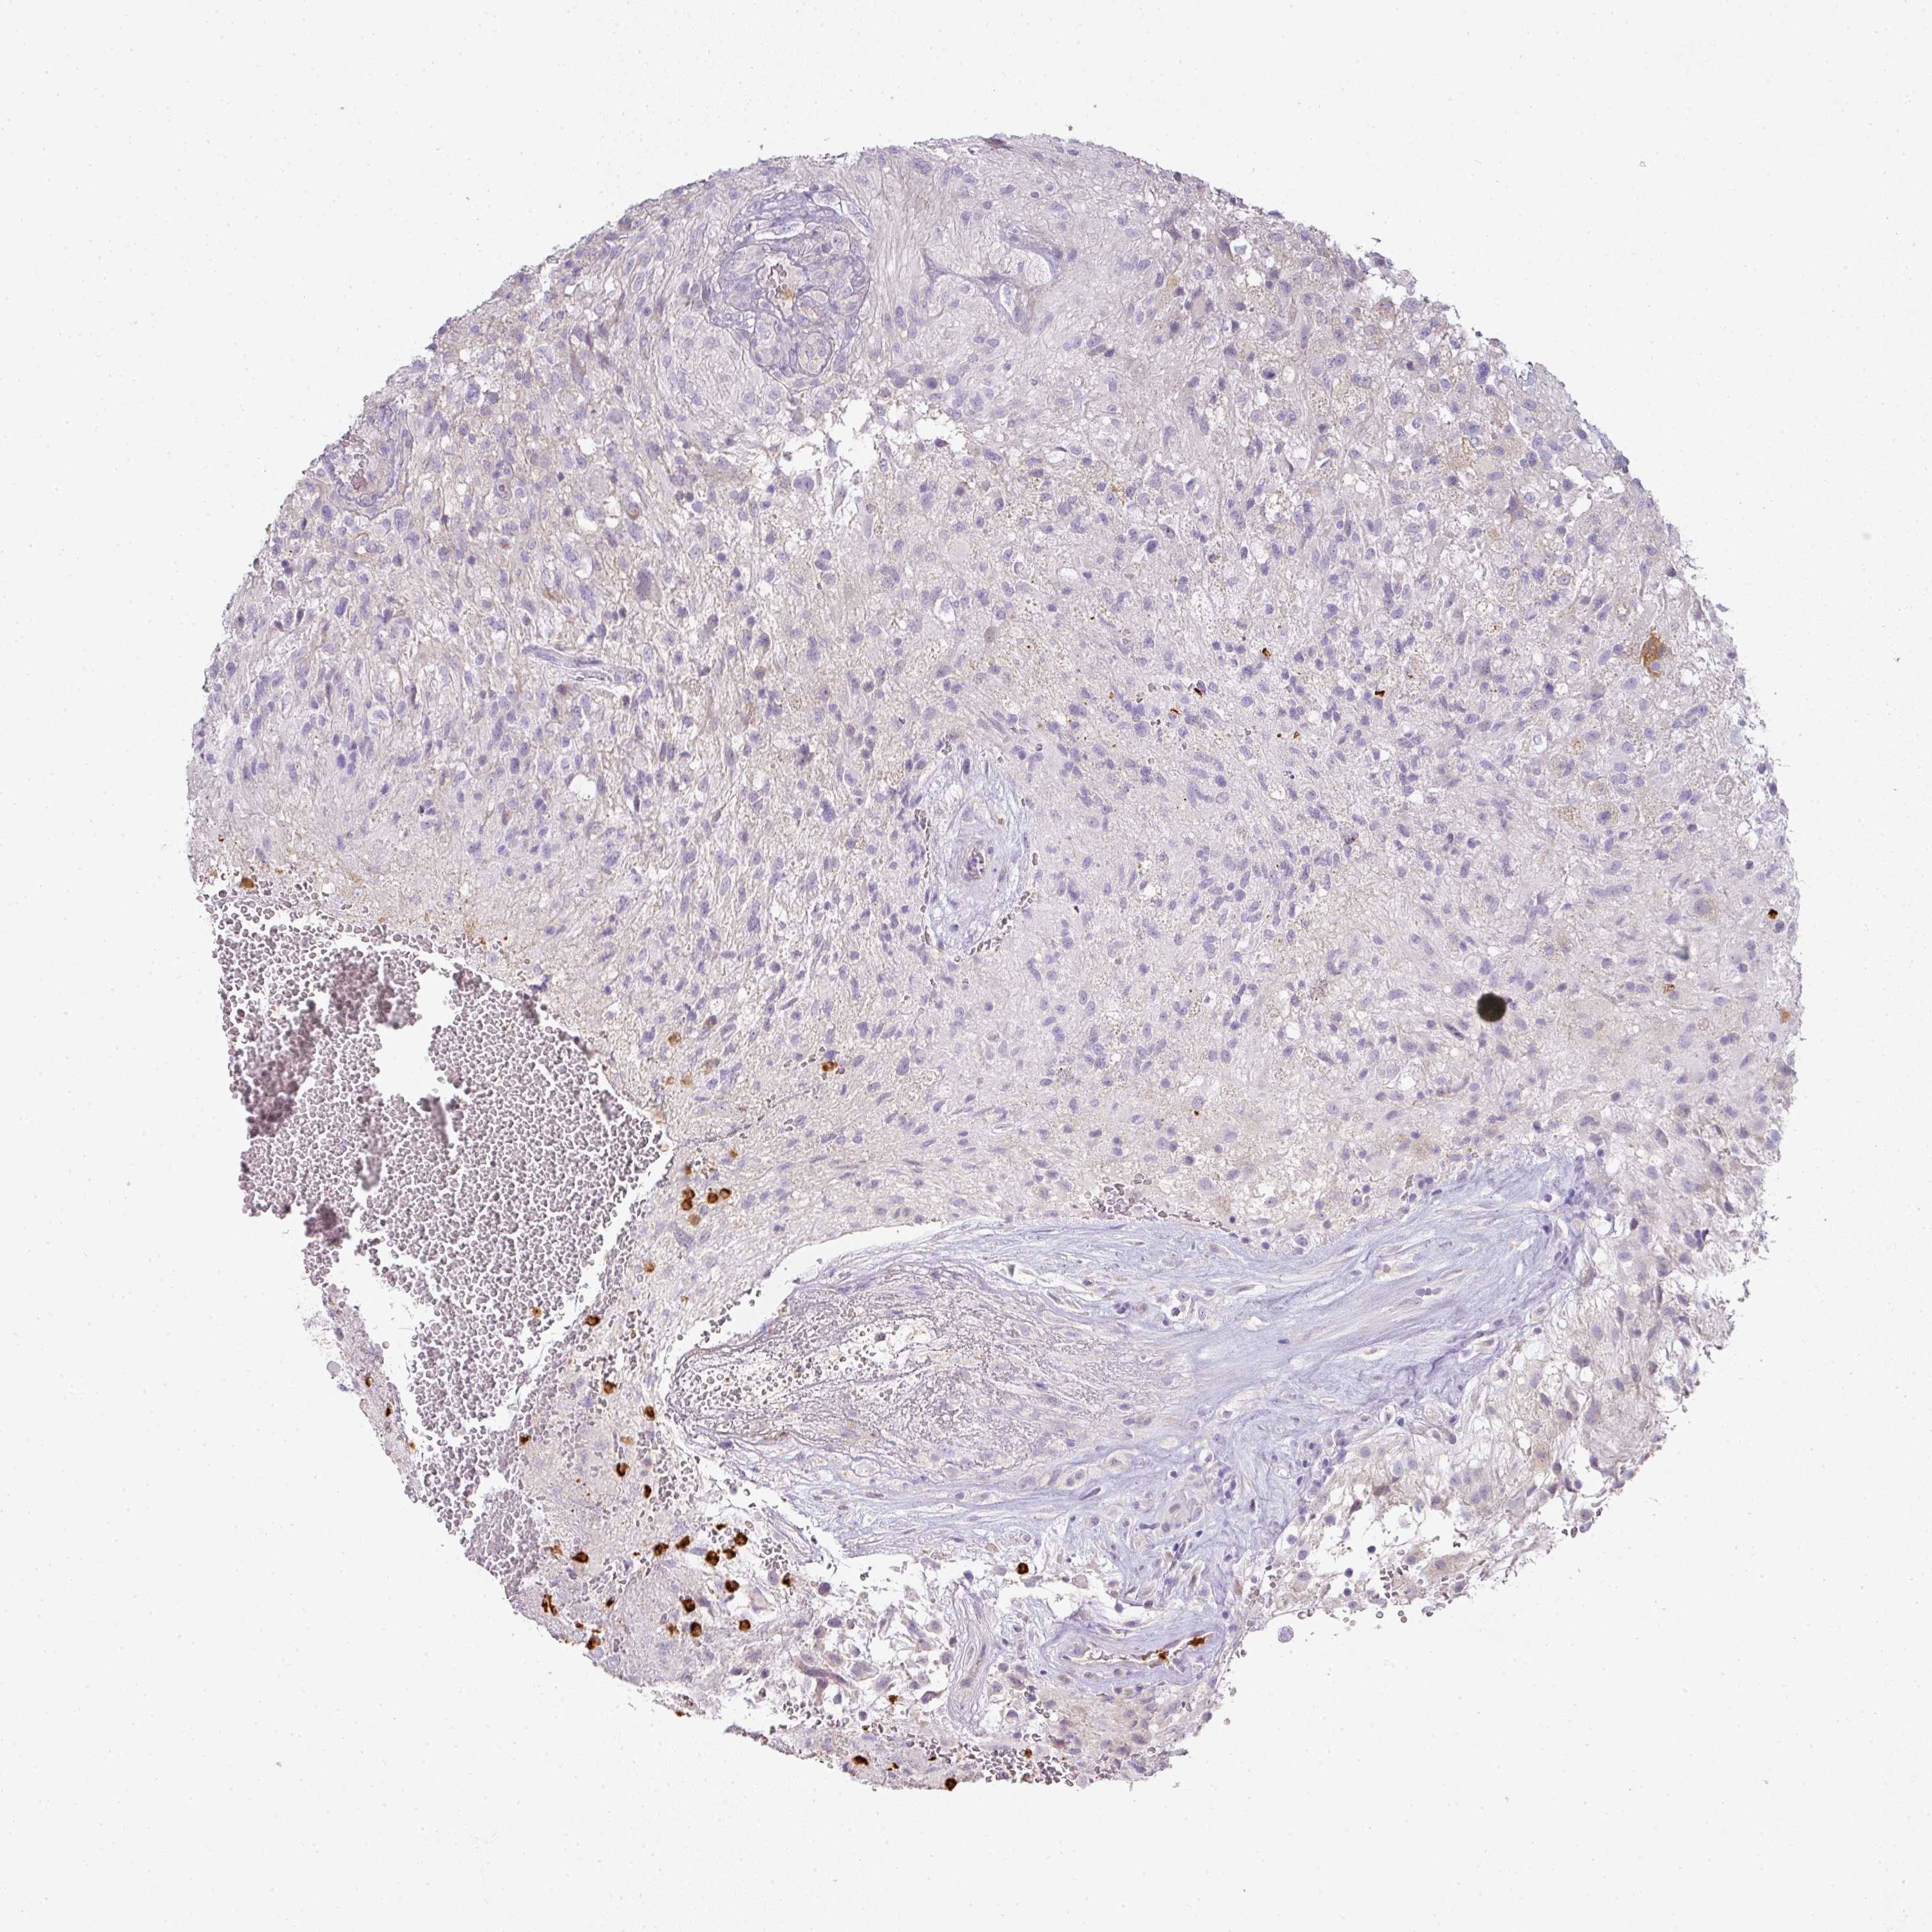

GLIOMA - Protein expressioni

A mouse-over function shows sample information and annotation data. Click on an image to view it in a full screen mode. Samples can be filtered based on level of antibody staining by selecting one or several of the following categories: high, medium, low and not detected. The assay and annotation is described here.

Note that samples used for immunohistochemistry by the Human Protein Atlas do not correspond to samples in the TCGA dataset.

Antibody stainingi

Antibody staining in the annotated cell types in the current human tissue is reported as not detected, low, medium, or high, based on conventional immunohistochemistry profiling in selected tissues. This score is based on the combination of the staining intensity and fraction of stained cells.

Each image is clickable and will lead to virtual microscopy that enables deeper exploration of all samples and also displays staining intensity scores, fraction scores and subcellular localization as well as patient and tissue information for each sample.

Antibody HPA051894

Staining

High

Medium

Low

Not detected

Intensity

Strong

Moderate

Weak

Negative

Quantity

>75%

75%-25%

<25%

None

Location

Nuclear

Cytoplasmic/membranous

Cytoplasmic/membranous,nuclear

Glioma, malignant, High grade

Glioma, malignant, Low grade

Glioblastoma, NOS